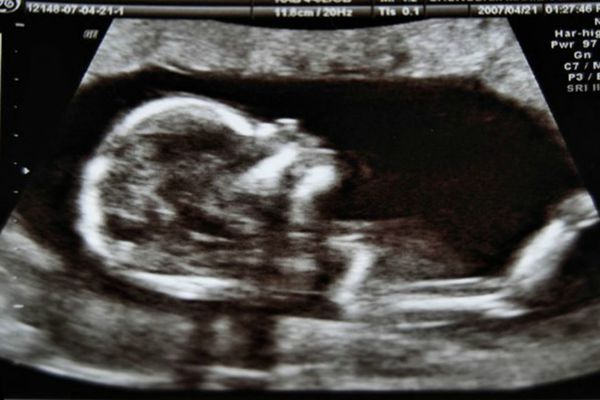

Al primer grupo le pidieron tomar una cápsula de col rizada en polvo y al otro una zanahoria. Ambos experimentos se realizaron al noreste de Inglaterra y 20 minutos antes de una ecografía. El equipo también examinó escaneos de 30 mujeres, tomados de un archivo, a quienes no se les dio ninguna cápsula, informó The guardian.

En general, los investigadores examinaron 180 escaneos de 99 fetos a las 32 semanas y a las 36 semanas o en ambos momentos.